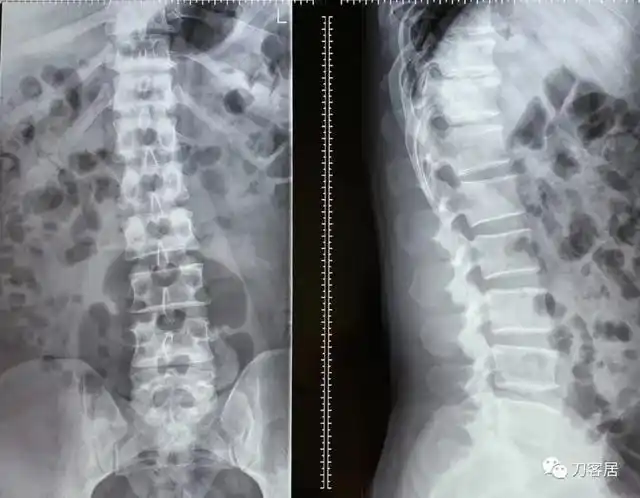

我的门诊病历:腰5骶1椎间盘突出症,保守治疗

腰椎间盘突出合并腰椎管狭窄症

腰椎间盘突出症治疗